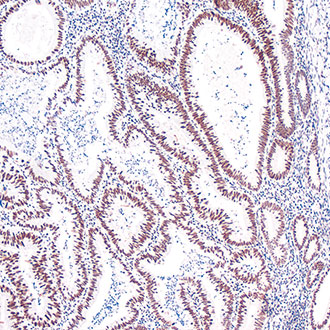

IHC

免疫组织化学(IHC)